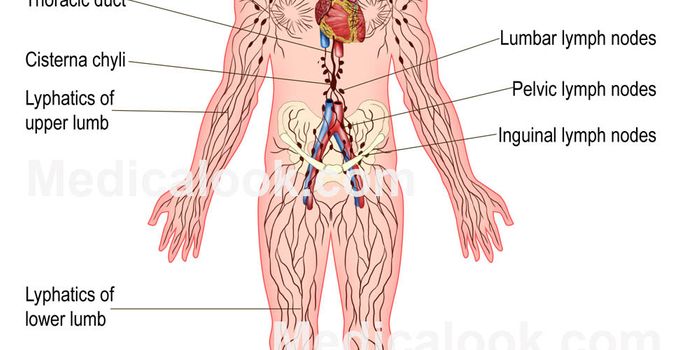

MAY 21, 2015Genetics & GenomicsComposed of lymph vessels, lymph nodes and organs, the lymphatic system absorbs excess fluid and returns it to the blood ...